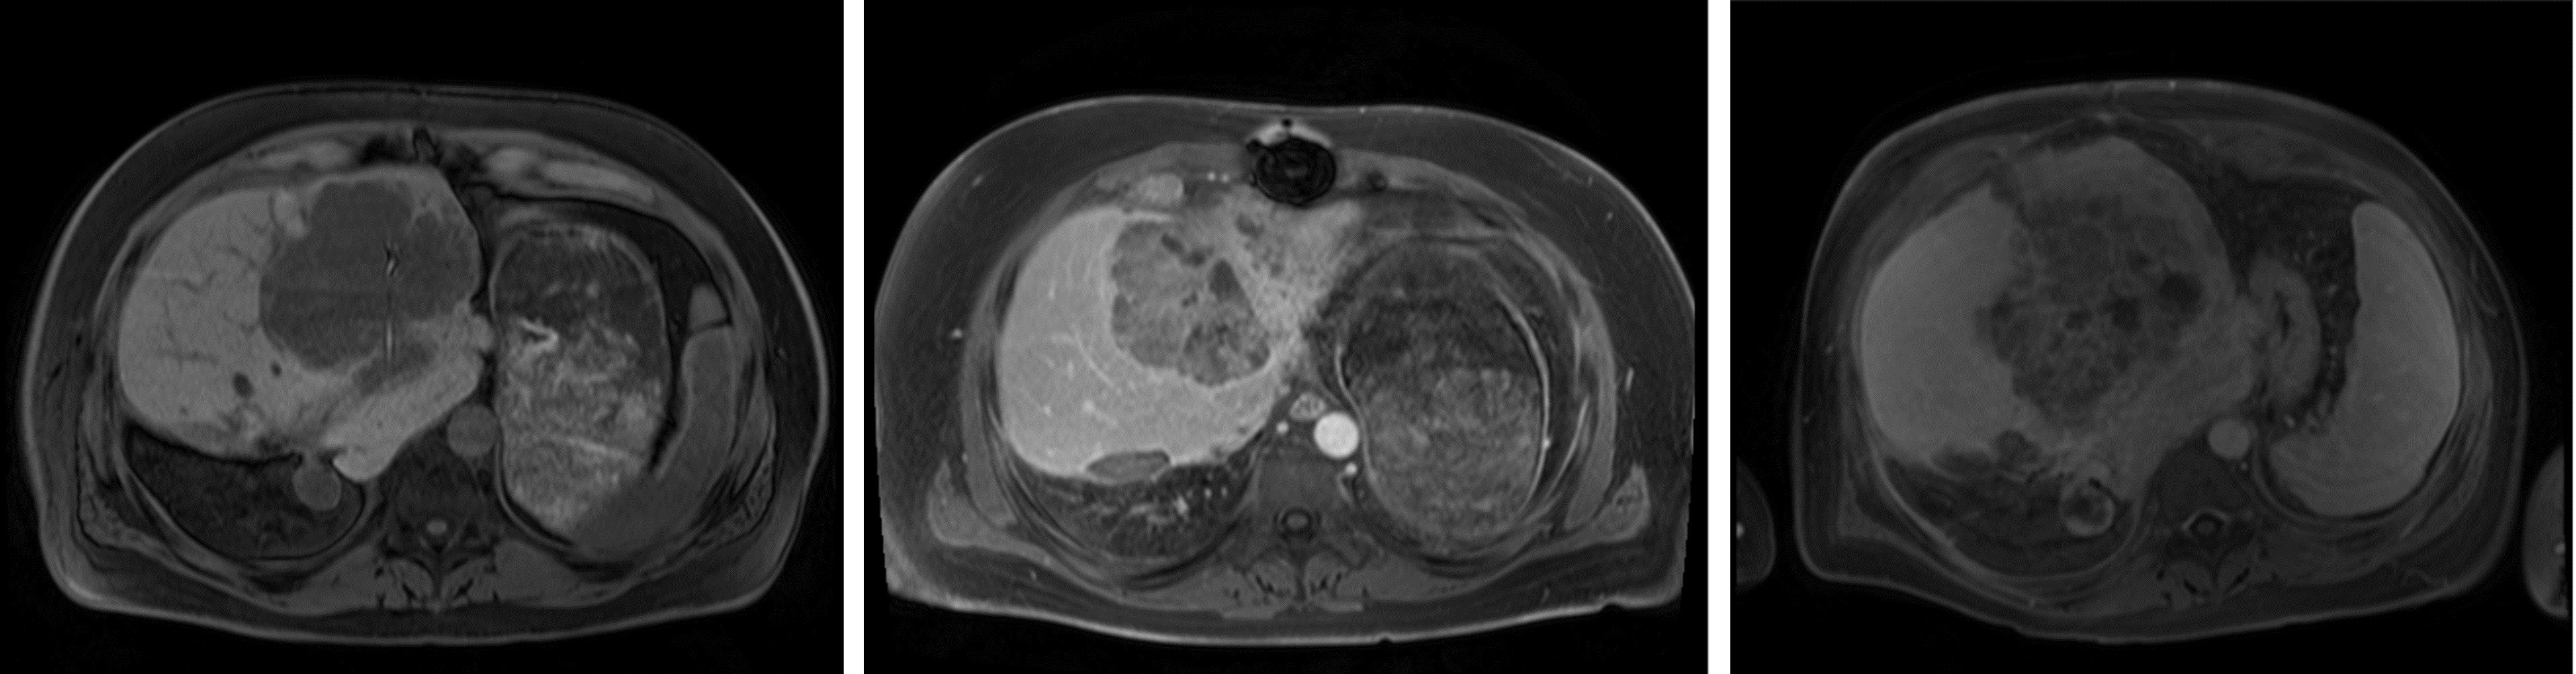

The segmentation performance of the MRI Dropout and MRI Ensemble models improved on that of the MRI UNETR by averaging the predictions (paired t-tests for HD, Dropout, Ensemble; Table 3). Thresholds for OOD detection were set at 95% DSC for all models except the MRI+ UNETR. This model only produced one DSC over 95%, so the threshold was lowered to 80%. 13 images determined to be OOD were shared across the MRI UNETR, MRI Dropout, and MRI Ensemble models. MRI+ UNETR and MRI+ nnU-net performed similarly on MRI+, with MRI+ UNETR achieving a lower HD and MRI+ nnU-net achieving a higher NSD (paired t-tests, all tests). Figure 2 displays visual examples of the segmentation quality of the MRI UNETR.

Paired with MD, all dimensionality reduction techniques resulted in improvements in the AUROC (t-tests, UMAP/MRI+ UNETR, all other tests; Table 4). On the MRI models, PCA achieved the best performance, outperforming average pooling by 0.14 (0.06)% AUROC and 535.11 (903.70) seconds. For CT nnU-net, UMAP achieved the best AUROC, outperforming average pooling by 0.09. Figure 2 displays MDs computed on PCA-reduced features, along with the corresponding segmentations. In this figure, higher MDs were associated with poor segmentation performance.